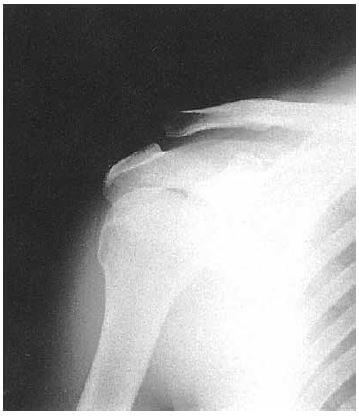

問題102.23歳の男性。バイク走行中転倒し右肩を強打した。右肩部の隆起に気づき来所した。右鎖骨外端が上方突出している。肩の水平外転は保持でき、軋轢音は認めない。単純エックス線写真を下に示す。

考えられるのはどれか。

1.鎖骨外1/3部骨折

2.棘上筋腱断裂

3.肩鎖関節上方脱臼

4.肩関節烏口下脱臼

解答3

解説

・23歳の男性。

・バイク走行中転倒:右肩を強打。

・右肩部の隆起に気づいた。

・右鎖骨外端が上方突出している。

・肩の水平外転は保持でき、軋轢音は認めない。

・単純エックス線写真:肩鎖関節の連続性が絶たれている。

→本症例は、肩鎖関節上方脱臼が疑われる。ほかの選択肢が消去できる理由も上げられるようにしよう。

🔸病態の理解(背景)

受傷機転:バイク転倒 → 肩峰部への直接打撃(肩を地面に強打)

結果:肩峰が下方へ押し込まれ、鎖骨外端が上方へ飛び出す。

臨床所見:

肩鎖関節部の腫脹と圧痛

鎖骨外端の上方突出(ピアノ鍵症状)

肩関節の水平外転・回旋が保たれる(=肩関節自体は脱臼していない)

X線所見:

→ 鎖骨外端が肩峰より明らかに上方に位置(肩鎖間距離の拡大)

→ 烏口鎖骨靭帯の断裂を伴うことが多い。

1.× 鎖骨外1/3部骨折より優先されるものが他にある。なぜなら、本症例から軋轢音は認めないため。また、単純エックス線写真には、鎖骨の連続性は保たれている

2.× 棘上筋腱断裂より優先されるものが他にある。なぜなら、本症例から右肩部の隆起(外観の変化)が生じているため。棘上筋腱板断裂では、外観変形はほとんど見られない。

3.〇 正しい。肩鎖関節上方脱臼が最も疑われる。なぜなら、なぜなら、鎖骨外端が上方に突出(ピアノキー症状)し、肩の水平外転保持が可能であり、X線で鎖骨が肩峰より明らかに上に位置しているため。

4.× 肩関節烏口下脱臼より優先されるものが他にある。なぜなら、本症例から肩関節烏口下脱臼の症状がみられないため。

・烏口下脱臼とは、肩関節前方脱臼(約90%)のひとつである。上腕骨頭が肩甲骨関節窩から前方に脱臼した症状で、①烏口下脱臼と②鎖骨下脱臼に分類される。関節全体を覆う袋状の関節包と靭帯の一部が破れ、突き出た上腕骨頭が烏口突起の下へすべることで起こる脱臼である。介達外力が多く、後方から力が加わる、転倒するなどで手を衝くことで過度の伸展力が発生した場合(外旋+外転+伸展)などに起こる。症状として、①弾発性固定、②関節軸の変化(骨頭は前内方偏位、上腕軸は外旋)、③脱臼関節自体の変形(三角筋部の膨隆消失、肩峰が角状に突出、三角筋胸筋三角:モーレンハイム窩の消失)、④上腕仮性延長、⑤肩峰下は空虚となり、烏口突起下に骨頭が触知できる。